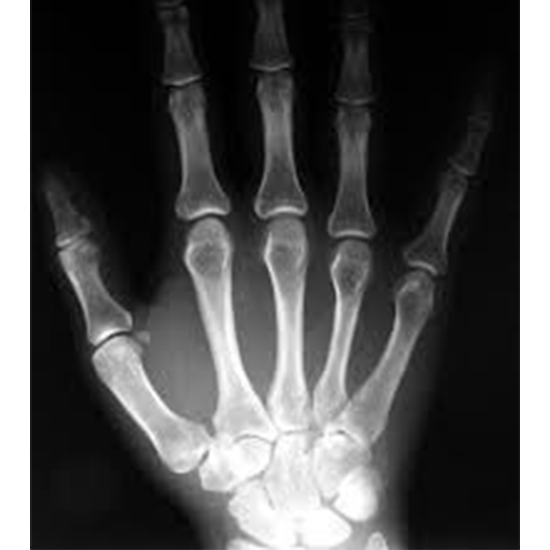

X-ray Right Thumb AP View

AP (anteroposterior) is one of the most common views used when assessing the thumb.

An X-ray of the thumb is used to visualize the bones of the thumb and the surrounding soft tissues (skin and muscles).

The AP thumb can be asked for many different reasons, such as a broken bone, signs of arthritis, or a foreign body. It is the best way to look at the metacarpal joint spaces and the places where ligaments attach. It may be the only way to see a gamekeeper's thumb, which is an injury to a ligament on the side of the joint.